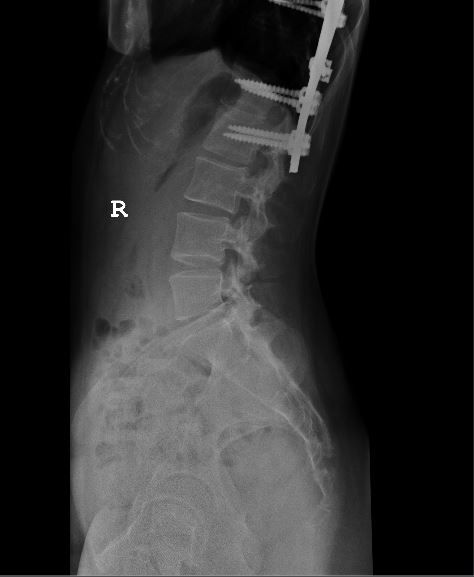

This is the implant inside my body. My spine was originally a ‘S’ shape spine.

It is not entirely straight now as you can see from the Xray..

The chiropractor also told me that I am actually putting additional stress on the other parts of the spine. 🙁 This is probably why my neck and head is always aching. sigh..